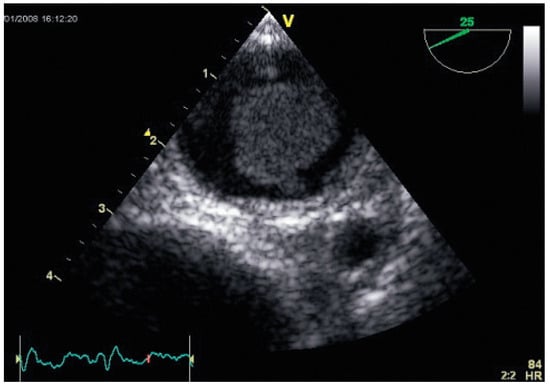

Interesting Images

Flottierender Thrombus in der Aorta Descendens

by Fritz Widmer and Attila Szönyi

Cardiovasc. Med. 2009, 12(1), 20; https://doi.org/10.4414/cvm.2009.01386 - 23 Jan 2009

Viewed by 46

Abstract

1995 hat die 63-jährige Frau eine tiefe Venenthrombose und einen zerebrovaskulären Insult mit Hemisyndrom links erlitten [...] Full article

Show Figures

Figure 1